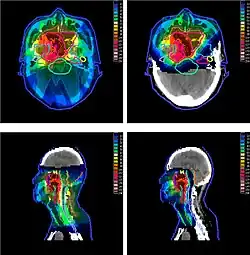

The figure at the right of the page shows how beams of X-rays (IMRT; left frame) and beams of protons (right frame), of different energies, penetrate human tissue. A tumor with a sizable thickness is covered by the IMRT spread out Bragg peak (SOBP) shown as the red lined distribution in the figure. The SOBP is an overlap of several pristine Bragg peaks (blue lines) at staggered depths.